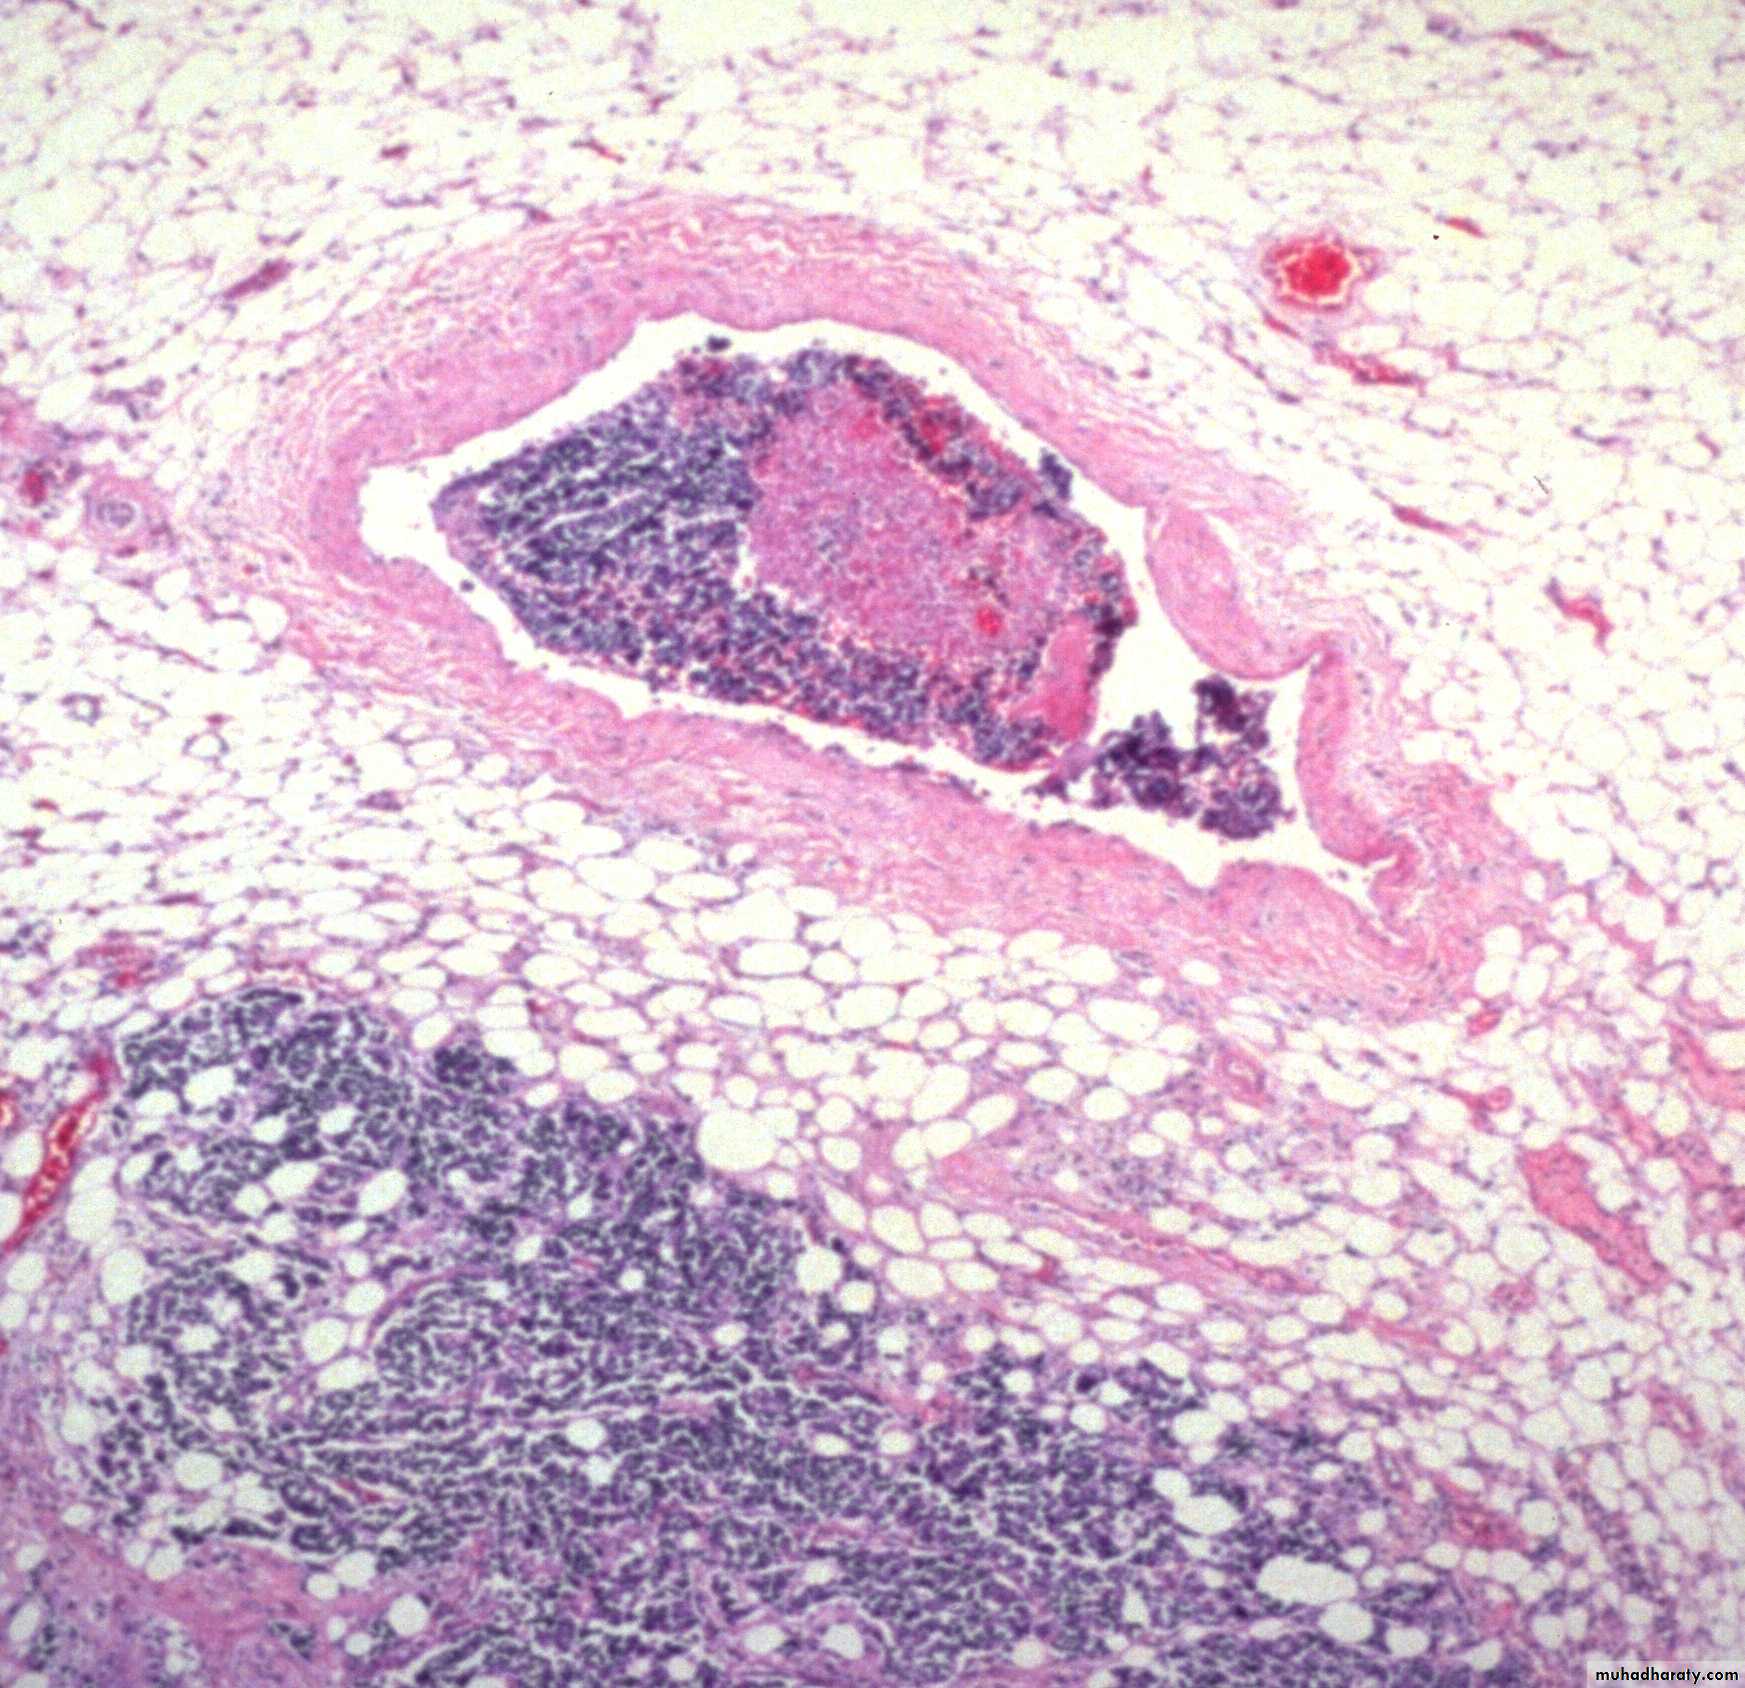

Blood (Haematogenous) Spread

Tumour cells are able to invade thin walled veins and grow along the venous system or embolize into the blood stream.The site of initial metastasis (first-pass organ)

depends on the venous drainage of the location of the

tumour.

Lung , liver and brain are the main organs of hematogenous spread for cancers.

Blood spread is main way for Sarcoma and later for carcinomaTranscoelomic Spread

III / vascular Invasion

The thin walls and poorly formed basement membranes of newly formed blood vessels allow the tumor cells to penetrate.

Once tumour cells are free within the lumen of the blood vessel they are carried into the circulation and lodge in a capillary bed.